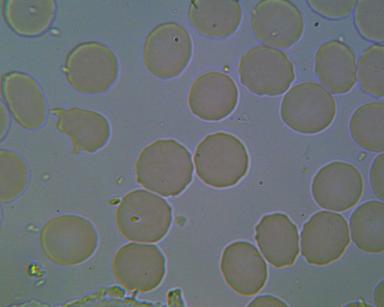

OBRAZ KRWI ŚWIADCZĄCY O ZAKWASZENIU ORGANIZMU:

1.RULONIZACJA I AGREGACJA ERYTROCYTÓW

To poważne zagrożenie zatorowo - zakrzepowe, co klinicznie może spowodować zapalenie naczyń obwodowych, zawał serca, udar mózgu a nawet nagły zgon. Agregacji i rulonizacji nie można stwierdzić tradycyjnymi badaniami diagnostycznymi.